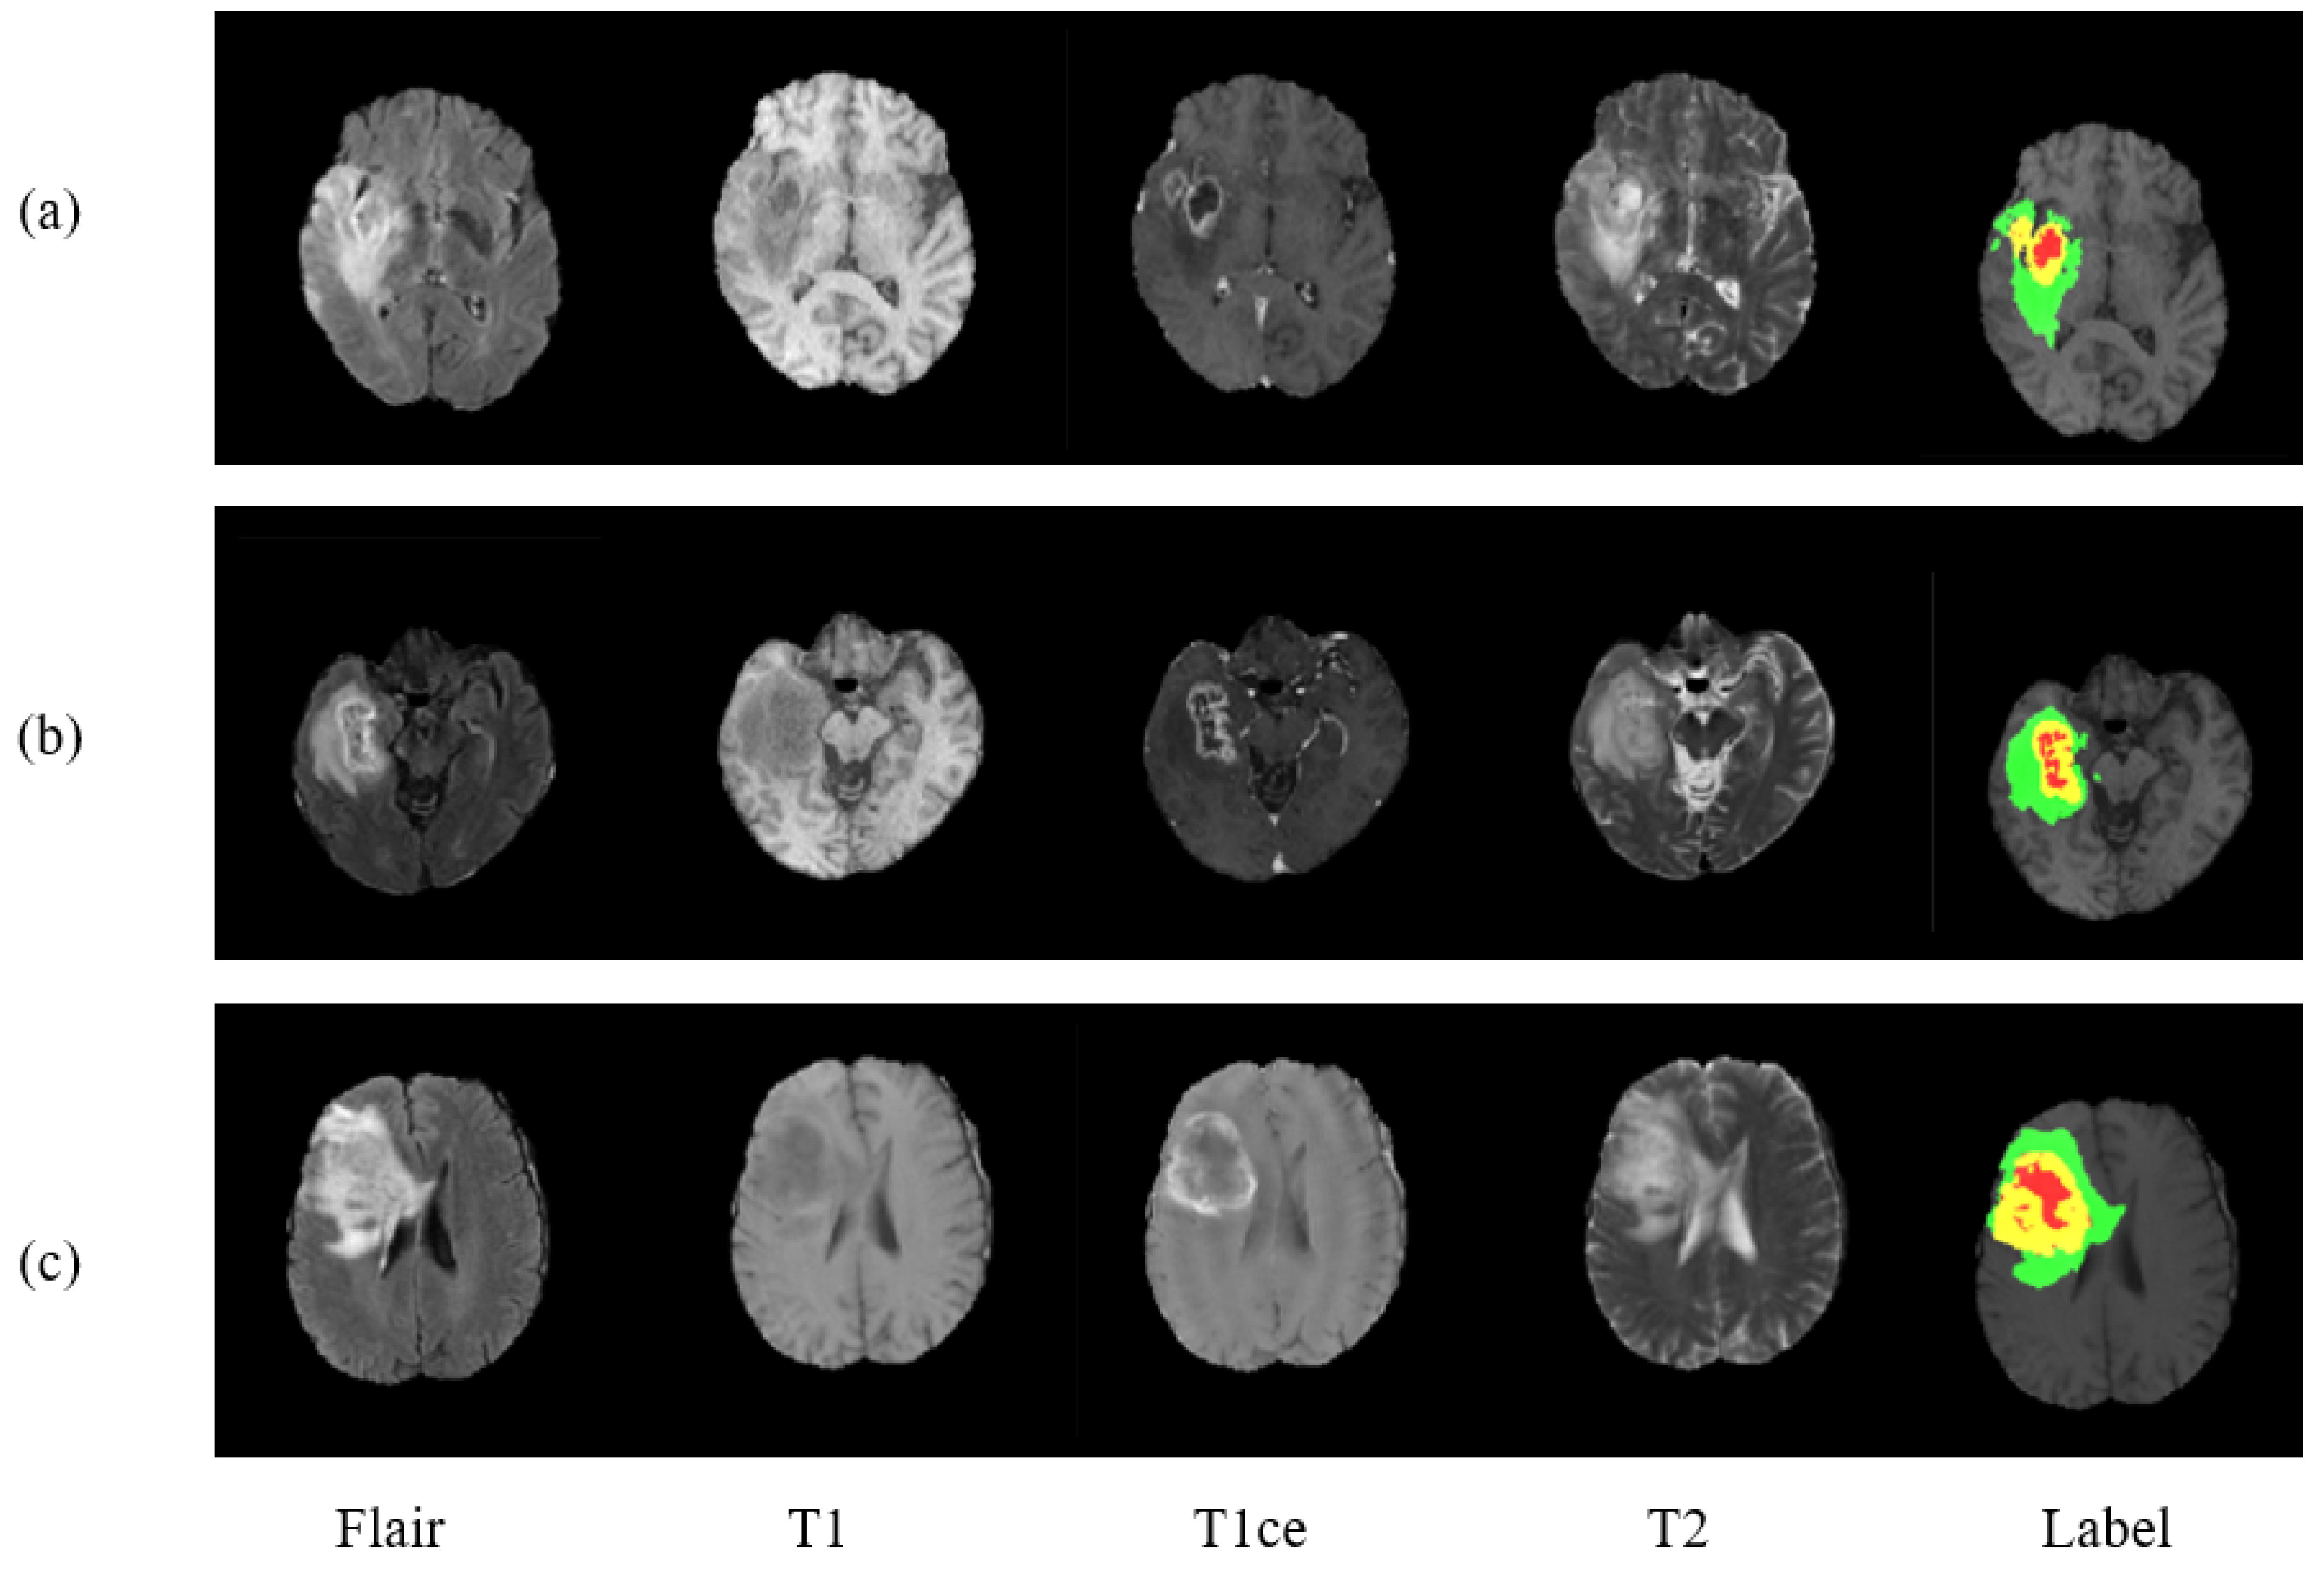

For the evaluation of proposed model, three benchmark databases are taken into consideration: BraTS 2017, Brats 2018, and BraTS 2019. These are publicly available benchmark databases used to train and evaluate the model. The BraTS2017 dataset is a collection of data from 285 glioma patients, consisting of 210 HGG and 75 LGG cases. The validation data set additionally includes images of 46 patients having an unknown grade. Unlike training data, validation data are not labeled, and results can only be generated using the online web of BraTS challenge. The dataset includes all four modalities for every patient as can be seen in Figure 1, where three data of three different patients is exhibited.

Figure 1. Presenting three MRI cases (ac) of brain tumor with four modalities and a label plots. From left to right are Flair, T1, T1ce, T2, and Label. In ground truth image each color represents different tumor class. Red for necrosis and non-enhancing, green for edema, and yellow for enhancing tumor.